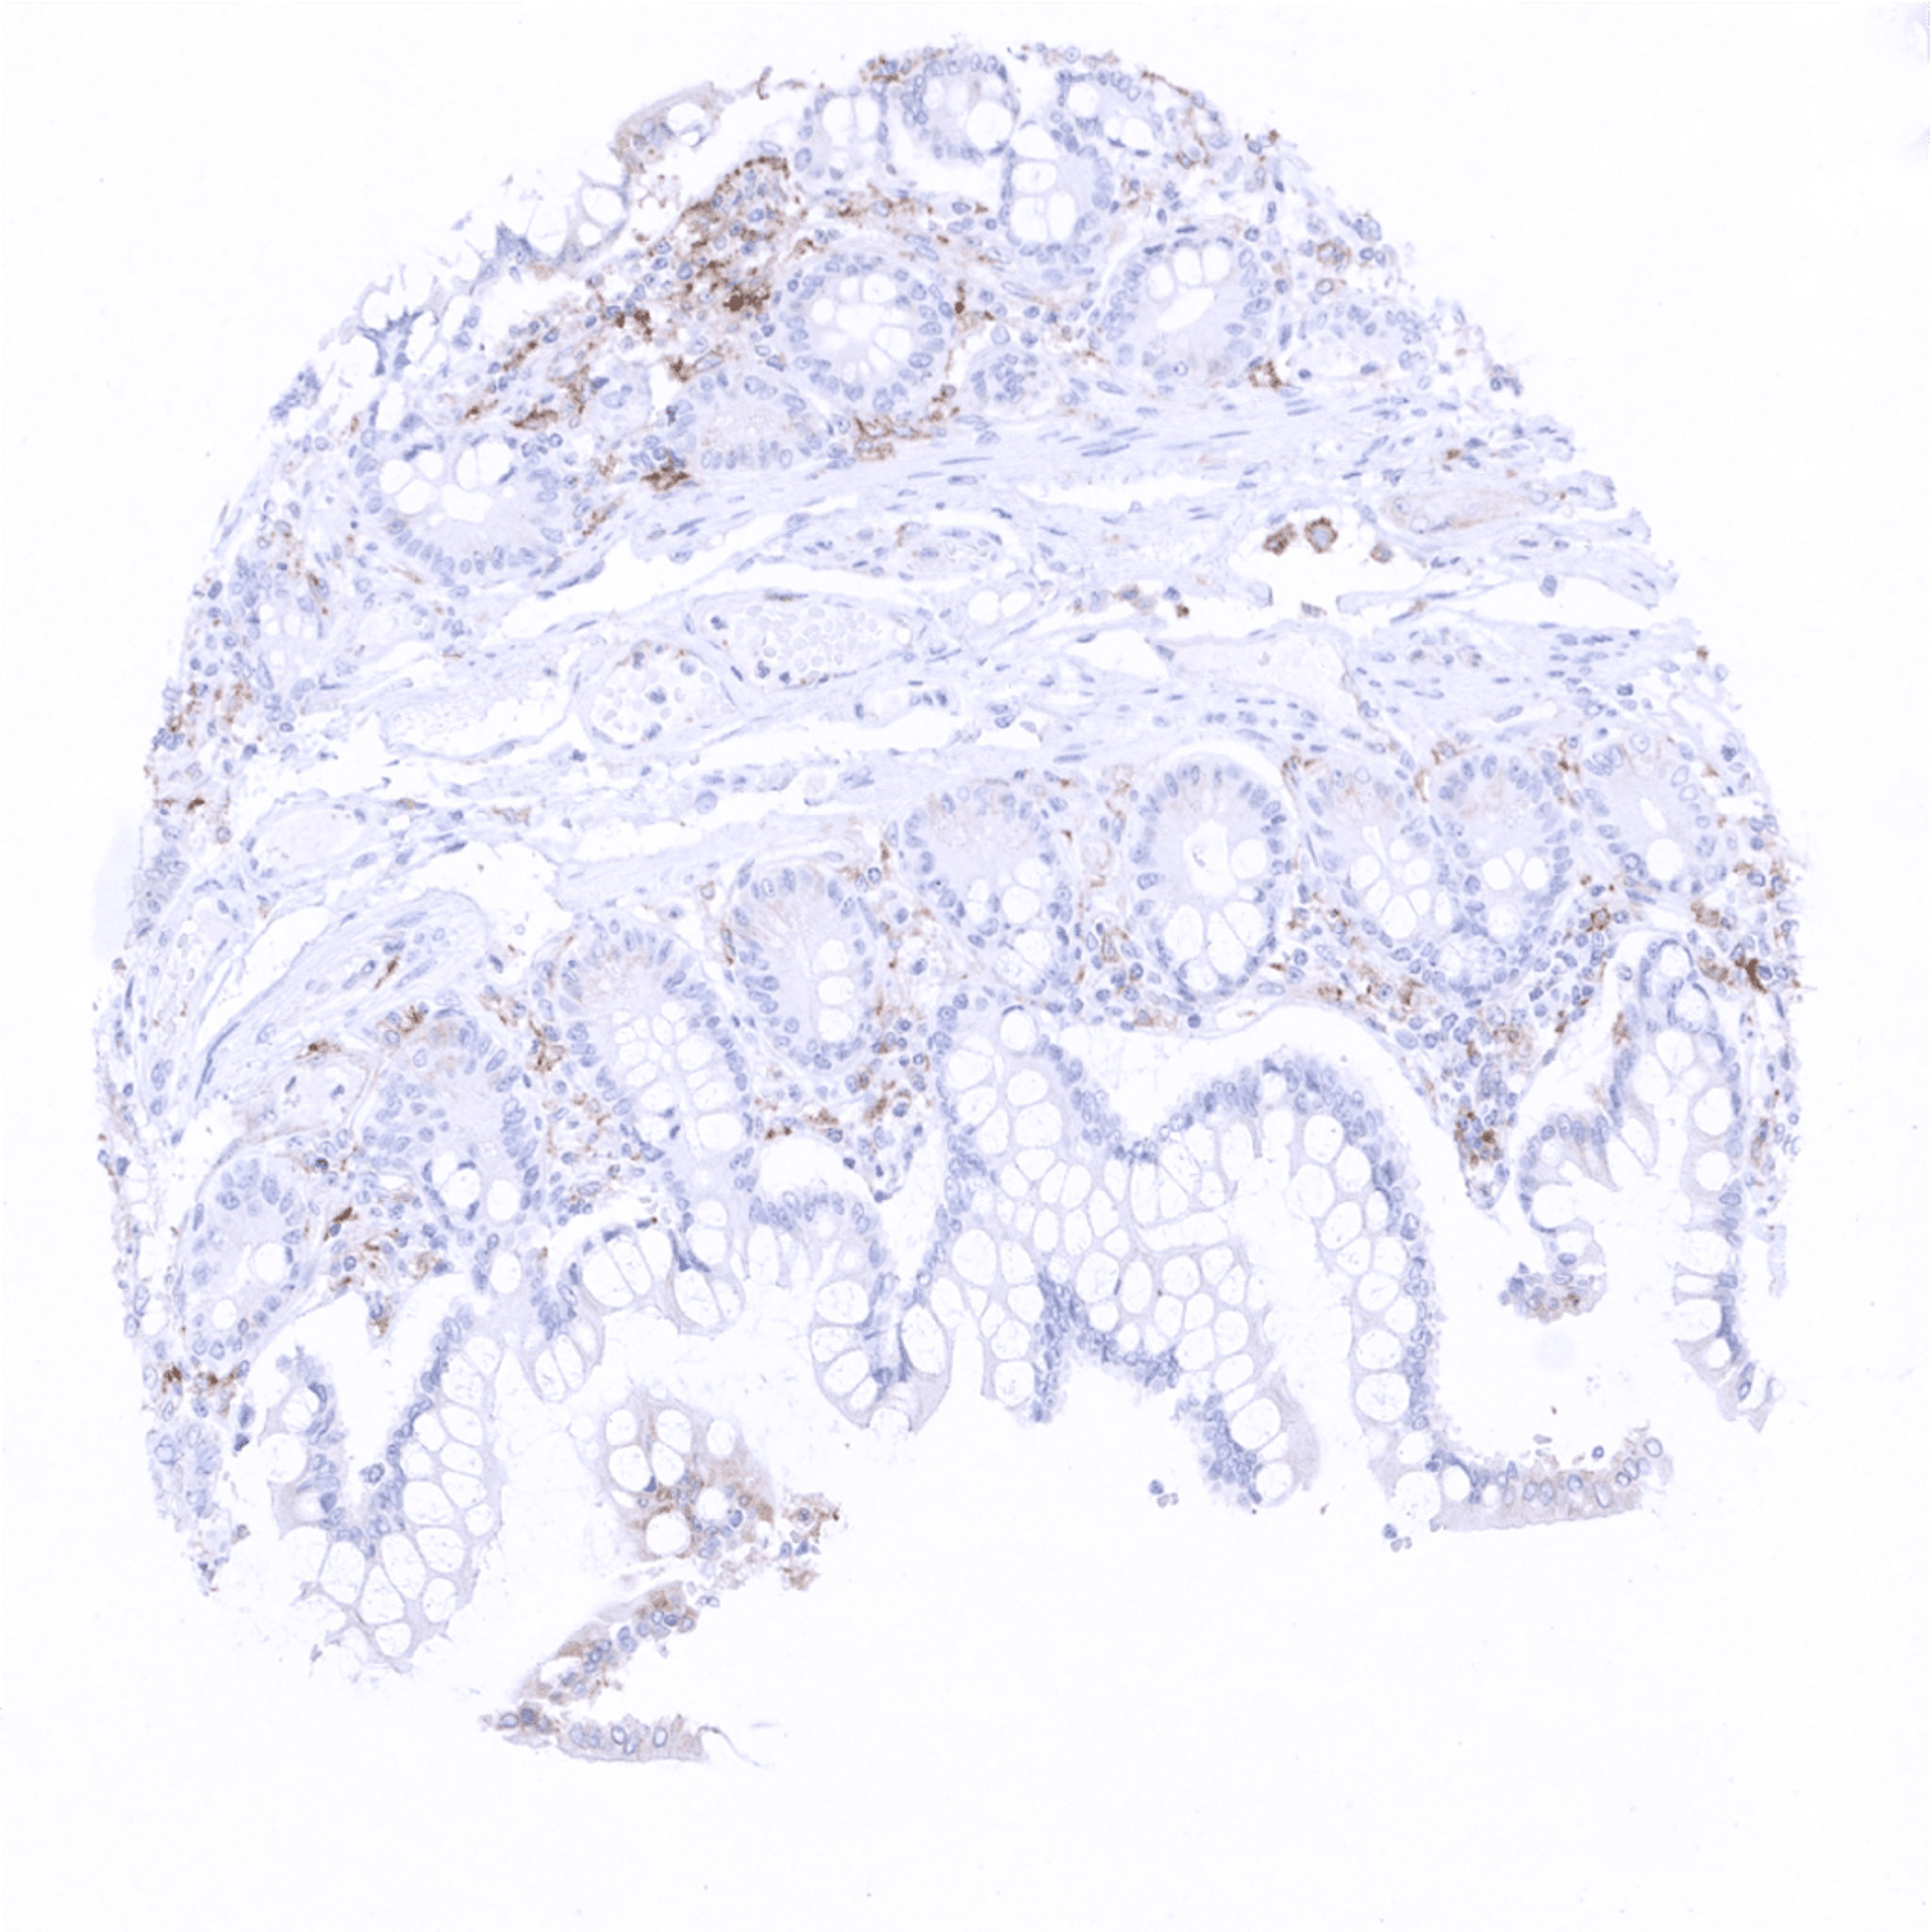

Ileum, mucosa

Ileum, mucosa – Few PD-L1 positive macrophages are seen.